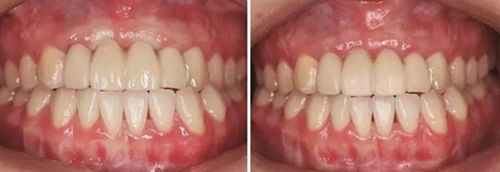

圖33 氧化鋯基底于口內(nèi)就位咬合正面觀 圖34 袖口正面觀

圖35 預(yù)粘接 圖36 戴入全瓷修復(fù)體正面觀

圖37 戴入全瓷修復(fù)體局部舌側(cè)觀 圖38 永久修復(fù)后微笑

圖39 永久修復(fù)后大笑